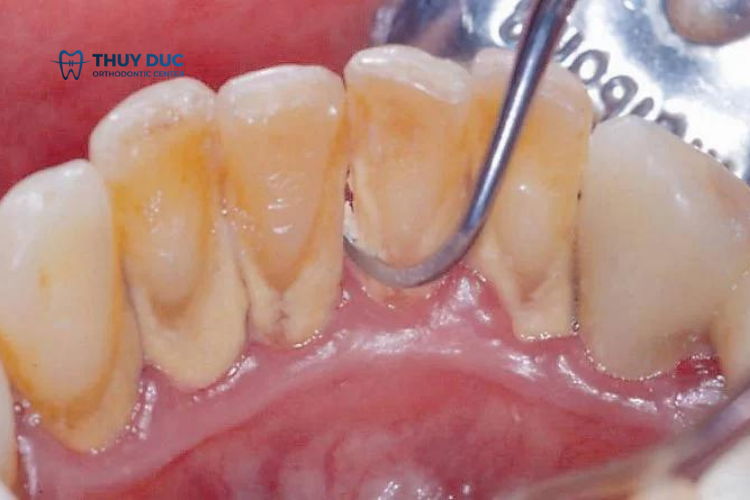

Cao răng (hay vôi răng) là một lớp cặn cứng hình thành trên bề mặt răng do mảng bám thức ăn kết hợp với khoáng chất trong nước bọt mà không được loại bỏ hoàn toàn. Cao răng ban đầu có màu vàng nhạt, nhưng theo thời gian có thể chuyển thành màu vàng đậm hoặc nâu do sự tích tụ thêm của các chất bẩn, thuốc lá, cà phê, hoặc trà.

Cao răng không chỉ gây mất thẩm mỹ mà còn là nguyên nhân dẫn đến nhiều vấn đề sức khỏe răng miệng như viêm nướu, viêm nha chu, và hôi miệng. Vì thế, việc lấy cao răng định kỳ là rất quan trọng. Thông thường, các bác sĩ khuyến cáo nên lấy cao răng 6 tháng đến 1 năm một lần để đảm bảo răng hạn chế mảng bám và giảm tác hại do mảng bám cao răng gây ra.

- Cao răng bám trên răng quá nhiều: Khi cao răng quá nhiều và lan sâu xuống nướu, bác sĩ sẽ phải tác động tới nướu – một mô mềm nhạy cảm ở khoang miệng. Đó là lý do tại sao cạo vôi răng bị ê buốt.